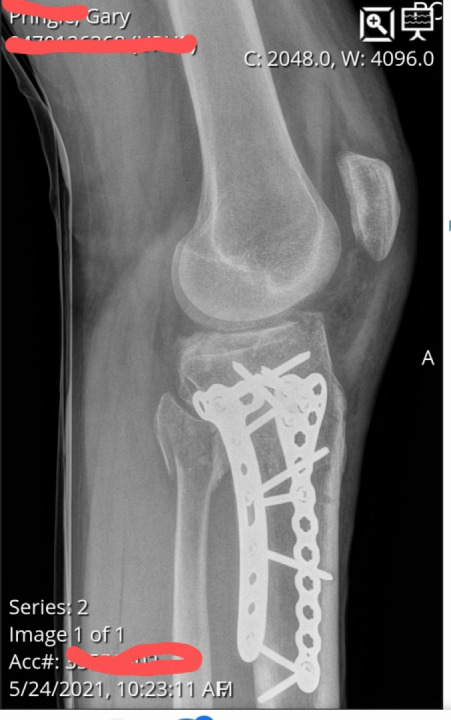

But then I hear tires squealing I look in my mirrors and everyone is stopping. next thing I'm on the Ground. bike is laying on me 3 people pick it up off me and 911 was called. Everyone stayed with me until the police and EMTS got there. I'm beat up sore and my feelings are hurt cause of it but I'm alive.